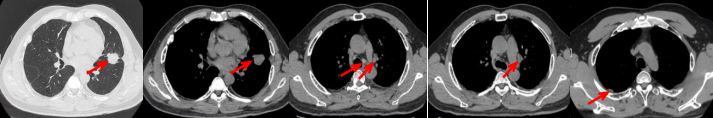

55岁男性,无吸烟史,有饮酒嗜好。2024年11月常规体检胸CT:左肺上叶占位性病变,大小约2.7×2.4cm,恶性可能大;左肺、左侧叶间胸膜及胸膜下多发微小结节,转移待除外。左侧胸腔积液,部分骨质改变。2024年12月初肺穿刺活检,病理:(肺)腺癌。NGS基因检测:CCDC6-RET(exon1-exon12)融合突变阳性(丰度:13.21%)。PD-L1表达阳性(TPS=35%,CPS=45)。

临床诊断:左肺上叶恶性肿瘤cT1cN2bM1a IVA期,肺门继发恶性肿瘤,纵隔继发恶性肿瘤,胸膜继发恶性肿瘤,胸腔积液。

治疗经过:2025.01开始口服普拉替尼(400mg,qd)。2025.03复查胸CT:左肺上叶、右肺上叶、左肺斜裂见多发实性结节影,长径范围约3-17mm,较大者大小约17mm×12mm,位于左肺上叶下舌段,可见分叶、毛刺、胸膜凹陷、棘状突起征象。纵隔内小淋巴结。评效PR,随访中。治疗期间未出现毒性反应。

2024.12

2025.03评效PR